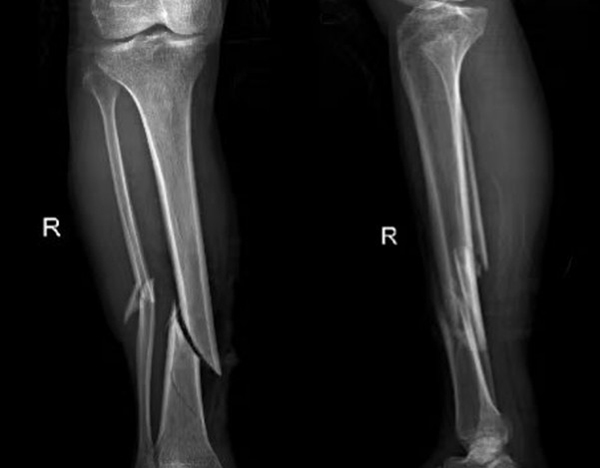

比如外傷患者,排查有無(wú)四肢骨折,X光片是首選,因?yàn)樗芸焖偾逦@示骨骼的連續(xù)性;而檢查關(guān)節(jié)內(nèi)的軟組織(如韌帶、半月板),則需要靠MRI,CT對(duì)此幾乎“無(wú)能為力”。所以,別主動(dòng)要求“升級(jí)”檢查,聽(tīng)從醫(yī)生的專業(yè)建議,才能既準(zhǔn)確又高效。